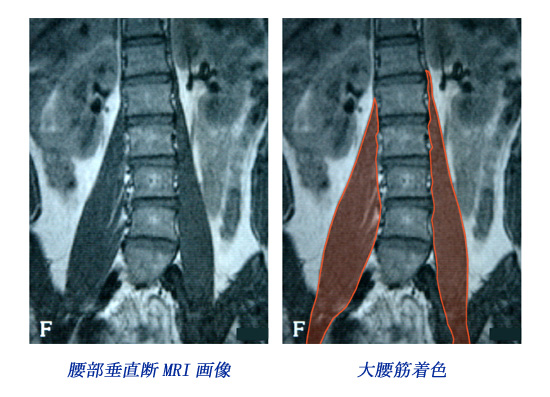

腰部MRI(大腰筋)画像

ヒントとして腰部MRI画像を掲載します。なおこのMRI画像は上部シルエット患者のものではありません。画像の左右に注意し、大腰筋に着目し熟慮してください。